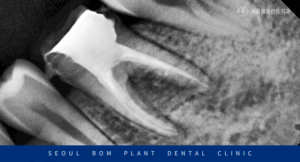

신경치료를 마무리한 치아를 보면

이렇게 신경관 안이 하얗게

치과재료로 메워져 있는 것을

확인할 수 있습니다.